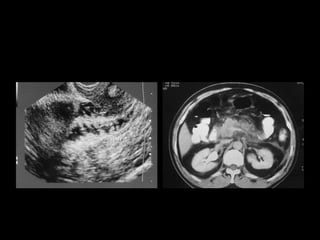

Radiografía de Tórax. Radiografías de abdomen simple de pie Radiografías contrastadas Ecografía abdominal Tomografía Resonancia Magnética

Radiografía de Tórax.Radiografías de abdomen simple de pie Radiografías contrastadas Ecografía abdominal Tomografía Resonancia Magnética